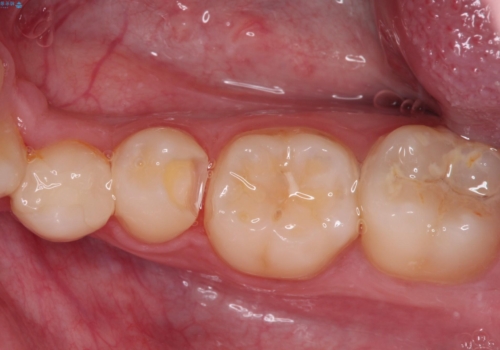

詰め物が欠けた セラミックインレーによる修復

- 以前治療した詰め物が欠けてしまったことを主訴として来院した患者様です。

食べ物がはさまったり、冷たいものがしみるといった症状がみられました。

むし歯の染め出し液と拡大鏡を用いて、むし歯がないことを確認し、

セラミックインレーにて修復することとしました。

食べ物がはさまりにくくなり、冷たいものがしみる症状もなくなり、大変満足していただきました。